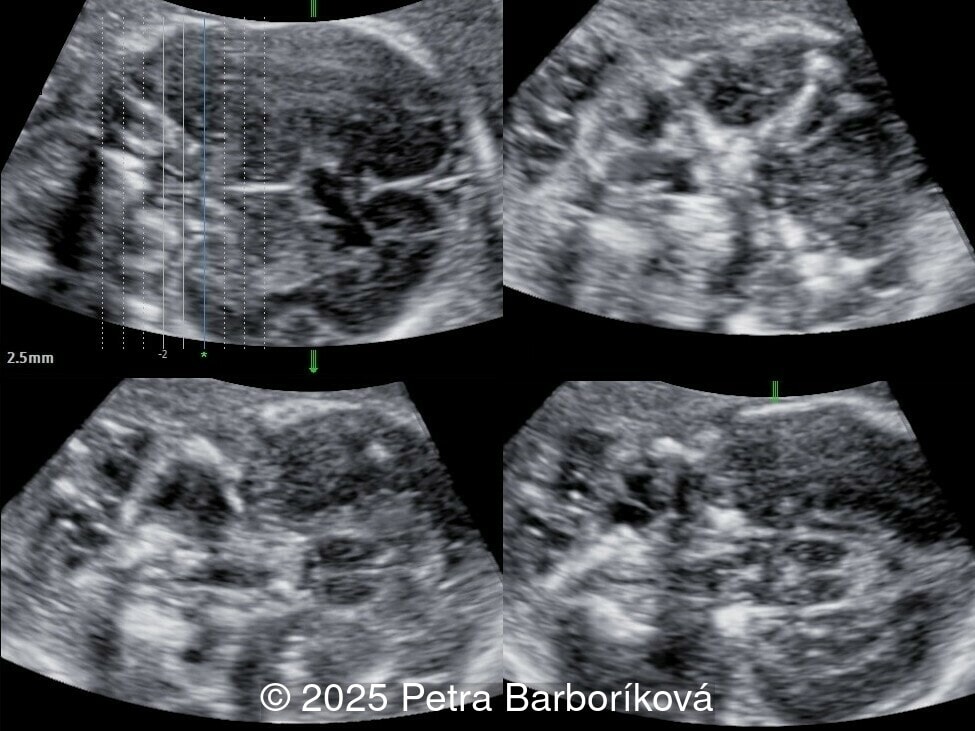

At 20 weeks, detailed ultrasound under conditions of severe oligohydramnios demonstrated absence of the typical box-shaped anechoic structure of the cavum septum pellucidum (CSP). The frontal horns of the lateral ventricles appeared narrow and pointed, giving the characteristic “bull’s horns sign.” Multiplanar and 3D reconstructions confirmed the presence of the corpus callosum, while the CSP was absent. Other midline and posterior fossa structures appeared normal. The optic chiasm was partially visualized, although assessment was limited by technical conditions. Fetal magnetic resonance imaging (MRI) was subsequently performed and confirmed isolated agenesis of the CSP with preserved corpus callosum and posterior fossa structures. The optic chiasm and pituitary stalk are visible in the sellar region, but the pituitary gland itself is not clearly identified in the sella turcica as it is a very small structure. No additional central nervous system anomalies were detected.